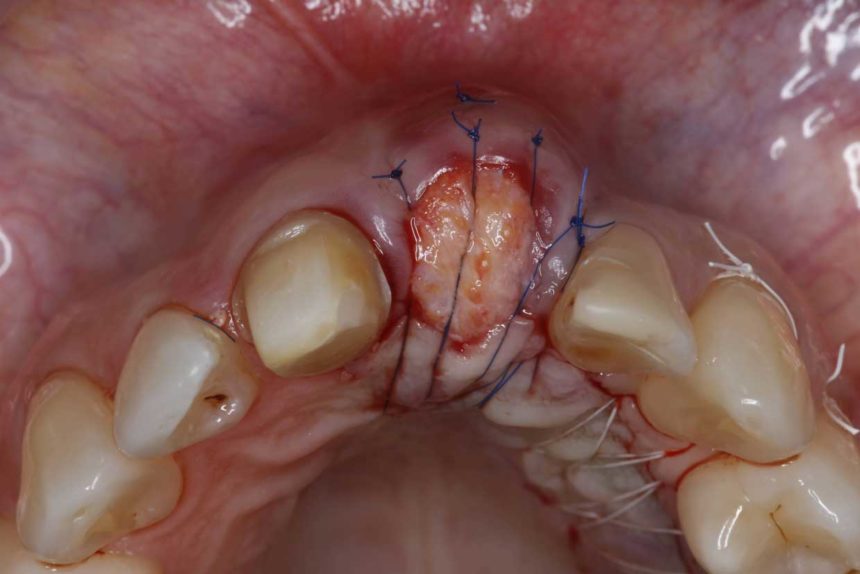

CONTEMPORARY SOFT TISSUE SURGERY FROM FLAP DESIGN TO WOUND CLOSURE

SOFT TISSUE QUALITY ENHANCEMENT AND INTERPROXIMAL ATTACHMENT GAIN

THE CORONALLY ADVANCED FLAP

SOFT TISSUE QUANTITY ENHANCEMENT AROUND TEETH AND IMPLANTS

TUNNELING TECHNIQUES ΙΝ SOFT TISSUE RECONSTRUCTION